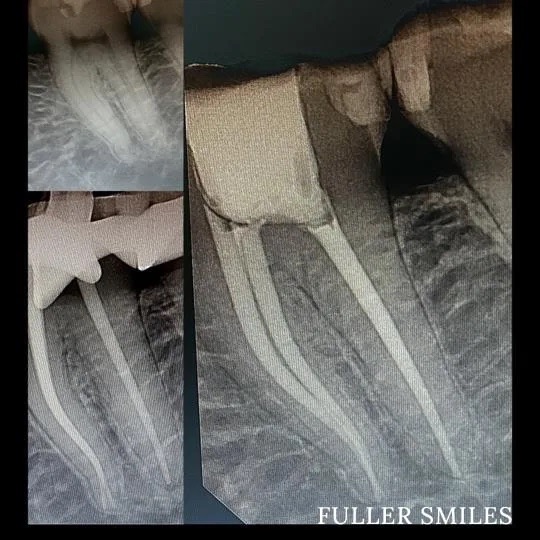

A thorough clinical exam, endodontic screening and proper x rays led to the diagnosis of irreversible pulpitis(inflamed pulp tissue) due to secondary dental caries with inflamed periodontal ligaments.

Our Dentists used the latest technology and highest quality products to finish this beautiful root canal followed by a post and core to give the tooth additional strength. The tooth was crowned after the root canal to restore function and aesthetics.